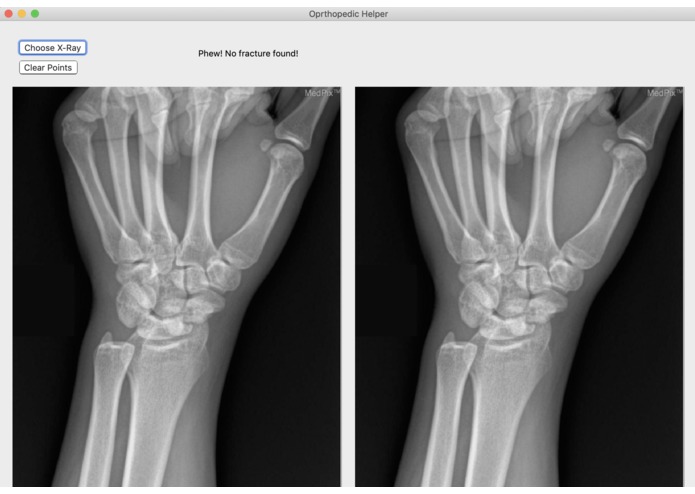

Broke Detector is a simple tool to help analyze the site of wrist injury. It helps doctors decide a) whether the bones are broken or not (which is admittedly very simple for humans, but not for computers) and b) provides tools such as a protractor to provide an objective measurement of how misaligned bones are. Broke Detector aims not to replace the orthopedist, but to aid them.

While we were very passionate about doing something involving the X-rays, there were a couple issues with our process. The common state-of-the-art solutions to a problem like this would be stuffing a bunch of data into a faster R-CNN and let it handle the detection. However, we lacked both the volume and consistency of data to make this a reality: many of the research papers that tackled this problem partnered with a medical office, which would provide them a lot of consistent and annotated images to work with. Because of the hodgepodge of different variables that differ with each image we ripped off of Google images, we had to use techniques like color thresholding, as the brightness of what was bone and what was background differed from image to image. Even now, the algorithm isn't quite perfect. It still struggles to detect fractures that are close to the end of the radius/ulna.

It works! Surprisingly. Certainly, I didn't expect to have this kind of success with a non-ML solution.